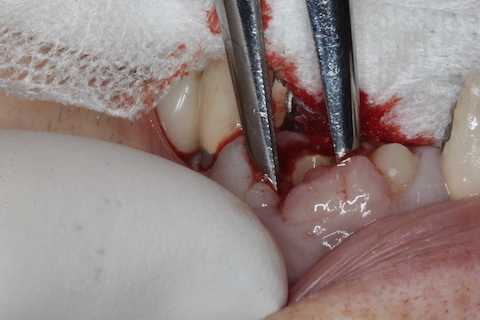

前回のつづきで、再植と化粧をする。さすがに歯なしでは寂しい。普通にズブズブと抜歯窩に再建した歯根を挿入する。あとは接着固定しながら、歯冠を再建していく。

前回のつづきで、歯根の再建と再植だ。歯根は裏表を逆に植え戻すことがあるが、やってみるとソケットにうまく戻らなかったので、やめることにした。綺麗にして既製のポストを入れて補強、再建していく。小さな破折片は使わなかった。歯根膜は失われているので、歯肉は下がるからだ。どうせ歯質が露出していれば虫歯になるだけだから、最初から充填しておいた方が良い。根尖口も開拡して充填する。準備ができたら再植する。